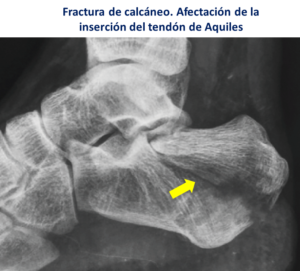

- Rotura en la inserción o fractura-avulsión: Ocurre en la inserción del tendón en el hueso del talón, puede desprenderse un fragmento óseo del calcáneo que en ocasiones requiere realizar una fijación con tornillos.